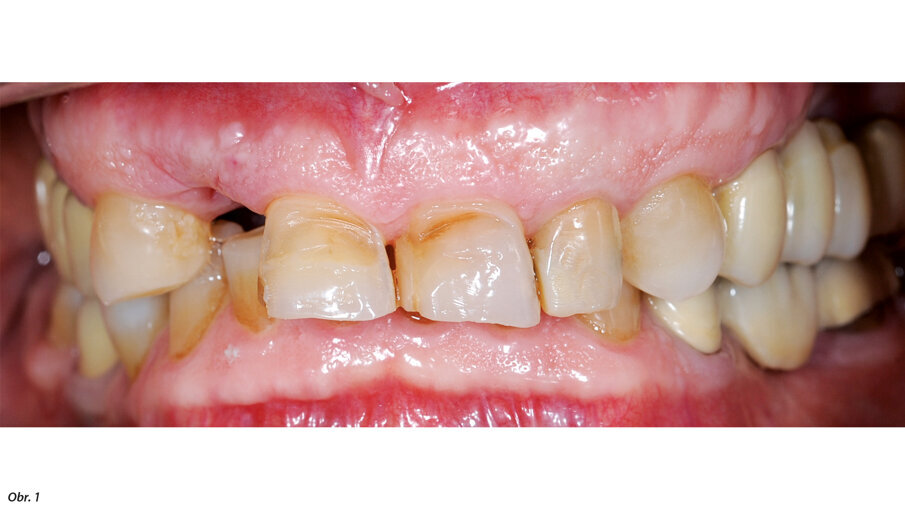

66letý pacient s non-inzulin dependentním diabetes mellitus a ischemickou chorobou srdeční se dostavil na ošetření parodontálního abscesu v oblasti radix relicta 12 a vícečetných fraktur stávajících náhrad (obr. 1–6). Během návštěvy byla zjištěna značná malokluze a ztráta VRO, abraze a fraktury stávajících náhrad i zbylých zubů a známky cervikální abfrakce. Pacient také trpěl mírnou bolestivostí svalů při palpaci, a to zejména v oblasti m. pterygoideus medialis et lateralis, sníženou schopností otevírání úst a slabými zvukovými fenomény v oblasti temporomandibulárních kloubů.